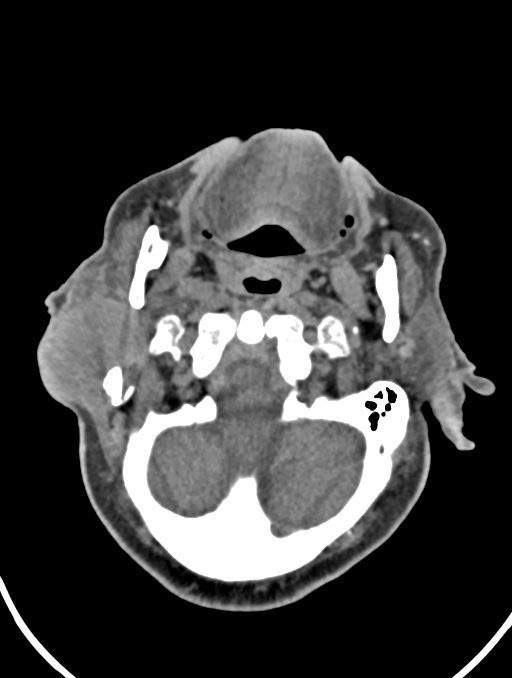

در سي تي اسکن اسپيرال نازو فارنکس با و بدون کنتراست (مولتي ديدکتور 16 با مقاطع ظريف و بازسازي هاي ساژيتال و کرونال):

– توده نسج نرمي به ابعاد mm 40 x 45 x 60 در ناحيه پاروتيد راست، با enhancement هتروژن پس از تزريق کنتراست مشهود است که مطرح کننده آدنوم پاروتيد مي باشد.

– شواهدي از تهاجم توده به استخوان و عروق اطراف مشهود نيست .

– کلسيفيکاسيون در ديواره شريان هاي کاروتيد دو طرف مشهود است .